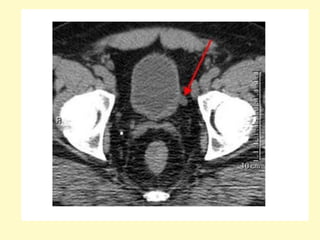

(a) Excretory urogram after 30 min shows severe dilatation of the right pelvocalyceal

system with cortical thinning and smooth obstruction of the right ureteropelvic

junction, (b) CTA with a maximum intensity projection technique demonstrates two

renal arteries originating from the aorta, an inferior aberrant artery (arrow) is crossing

over the ureteropelvic junction